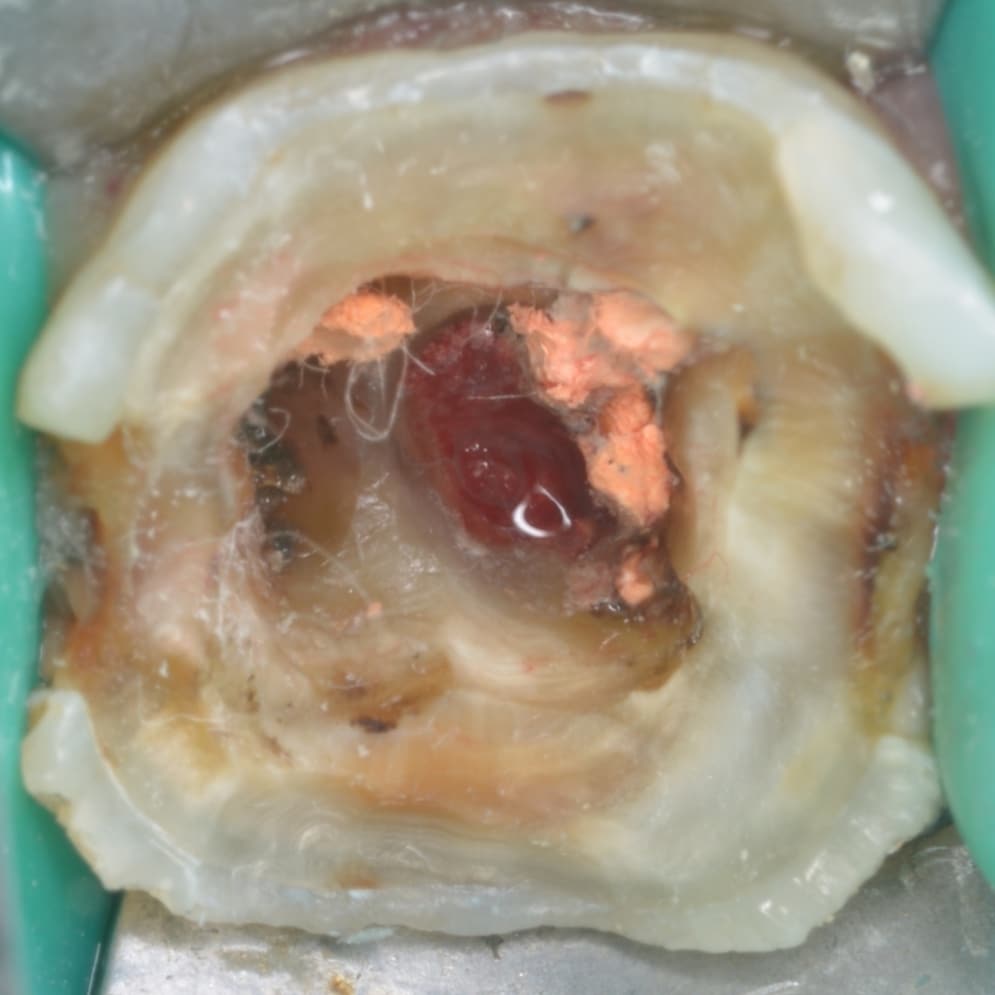

Initial situation

After removing old restoration

Removing old gutta percha showing perforation